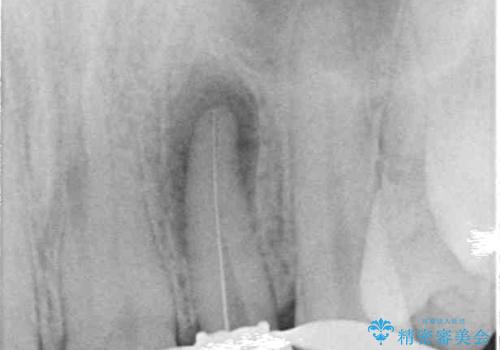

レントゲン写真から、大きくなった根尖病変が認められました。

根管治療後速やかに痛みが消退し、6ヶ月後のレントゲン写真では、根尖部の病変がほぼなくなっていることが分かりました。